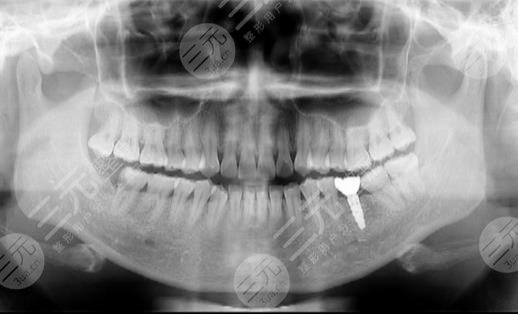

到醫(yī)院進行面診的時候,醫(yī)生先讓我咬了牙齒的模型,然后又拍了牙片,選擇了牙齒的種植體,一星期之后,我來到了醫(yī)院進行種植牙。整個種植牙的過程是很快的,而且因為打了局部mz也沒有任何的感覺。大家現(xiàn)在可以看到我的種植牙是十分成功的,而且看上去十分的潔白,跟周圍的牙齒形成了鮮明的對比。